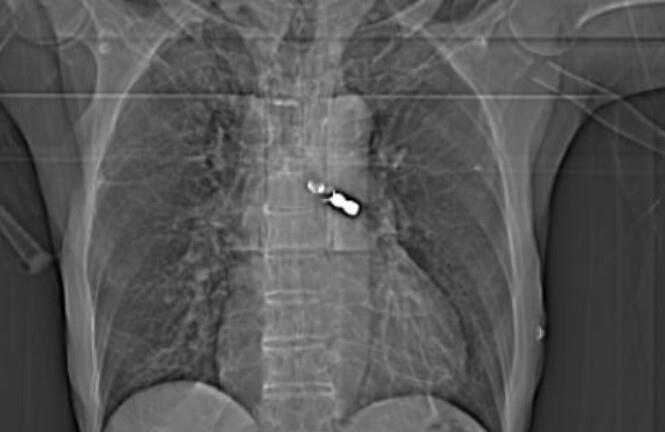

Củ cà rốt 20cm mắc kẹt trong trực tràng thiếu niên 16 tuổi

Báo Công Lý đưa tin, nam bệnh nhân 16 tuổi vào Bệnh viện Hoàn Mỹ Bình Dương trong tình trạng đau tức hậu môn do tự ý nhét dị vật là củ cà rốt vào và bị kẹt luôn trong đó. Khai thác bệnh sử được biết bệnh nhân tự ý nhét củ cà rốt vào hậu môn do tò mò và bắt chước các thông tin trên mạng để thử "cảm giác lạ".

Tuy nhiên sau đó, người bệnh không thể lấy củ cà rốt ra và đau nhức nên đến bệnh viện để được giúp đỡ. Ngay sau đó, các bác sĩ đã tiến hành gây mê và lấy thành công dị vật là củ cà rốt có đường kính khoảng 4cm, dài 20 cm.

Theo bác sĩ CKI Trần Duy Công - Trưởng khoa Ngoại tổng hợp của bệnh viện và cũng là người trực tiếp tiến hành thủ thuật, các trường hợp nhét dị vật kích thước lớn vào hậu môn có thể dẫn đến nguy cơ trầy xước niêm mạc hậu môn, nhiễm trùng, chảy máu hay thậm chí thủng trực tràng, tắc ruột, vỡ ruột rất nguy hiểm, thậm chí có thể tử vong.